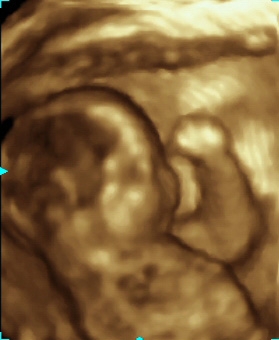

Standardowo badanie w 20 tygodniu ciąży wykonywane jest w technice 2D. Jest to aktualnie metoda najdokładniejsza w wykrywaniu ewentualnych anomalii. Dodatkowo można wykonać badanie w technice 3D i 4D, co pozwala na trójwymiarową wizualizację płodu.

Na tym etapie ciąży szczególnie ciekawe jest badanie w technice trójwymiarowej. Jeżeli tylko warunki techniczne badania są odpowiednie (położenie płodu, odpowiednia ilość wód płodowych), można bardzo dokładnie uwidocznić zarys twarzy płodu, kończyny, płeć. USG ginekologiczne W naszej poradni przeprowadzamy w pełnym zakresie badania USG narządu rodnego, zarówno przezbrzuszne, jak i przezpochwowe.